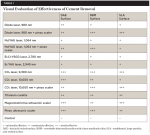

At the completion of treatment each implant surface was examined visually, and using a three-point scale, the effectiveness of the treatment for the removal of the cement was estimated (Table 1). The three-point assessment scale was as follows:

+ Minimal treatment effect = some cement removal from crest of implant threads, no cement removal from the concavities between threads (Figure 2 and Figure 3).

++ Moderate treatment effect = removal of cement from crest of implant threads, some cement removal between threads, but minimal exposure of the subjacent implant surface (Figure 4 and Figure 5).

+++ Mostly effective treatment = removal of cement from crest of implant threads and most of the cement between threads, with exposure of most of the subjacent implant surface (Figure 6 and Figure 7).

From a visual standpoint, none of the treatments was completely successful at removing all of the cement from the implant surfaces (Table 1). The SEM images supported the visual observations with respect to effectiveness of cement removal and expanded on these findings from the perspective of surface alterations.

The CO2 9300 nm laser visibly removed most of the cement on all three implant surfaces and showed minimal surface changes under SEM (Figure 6 and Figure 7), while the Er,Cr:YSGG and Er:YAG lasers and the Nd:YAG laser alone had a minimal effect on the cement and implant surface (Figure 2 and Figure 3). Cement removal by the CO2 10,600 nm laser as a monotherapy was variable depending on the surface tested.

The Ti curet, magnetostrictive scaler, piezo scaler, Nd:YAG + piezo scaler, and the CO2 10,600 nm + piezo scaler showed moderate to mostly effective treatment results, although scratches on the implant surfaces were observable. A flattening and smearing of the crests of the implant threads was apparent under SEM (Figure 4, Figure 5, Figure 8, and Figure 9). These effects were not evident when the two lasers were applied as a monotherapy.

Table 1 reveals that none of the treatment modalities was completely successful at removing all cement from the implant test surfaces. Post-treatment SEM evaluation was carried out to obtain magnified views of residual cement and assess damage to the implant surface that might have occurred as a result of treatment. The effectiveness of cement removal varied markedly, with the implants treated with the CO2 9,300 nm laser protocol being mostly free of cement (Figure 6 and Figure 7) and the Er,Cr:YSGG and Er:YAG lasers (Figure 2 and Figure 3) and Nd:YAG laser (as a monotherapy) being minimally effective. When used as part of a dual therapy in conjunction with the piezo scaler, the Nd:YAG, CO2 10,600 nm, and diode lasers were only marginally more effective than the piezo scaler alone.

The post-treatment SEM images revealed that surface damage varied and included scratching, flattening, smearing, and chipping of the crests of the implant threads. Additionally, both visually and under SEM, the diode laser, when used as a monotherapy, showed localized areas of carbonization and cement surface damage due to excessive heat.When used as a dual therapy with the piezo scaler, less damage was evident as the diode laser was not used alone for the total decontamination time. Although the damages noted might preclude osseointegration or soft-tissue adherence at specific sites on an implant, extensive damage that might interfere with re-osseointegration of an entire implant surface was not observed using any of the test instruments at the prescribed settings (Table 2).